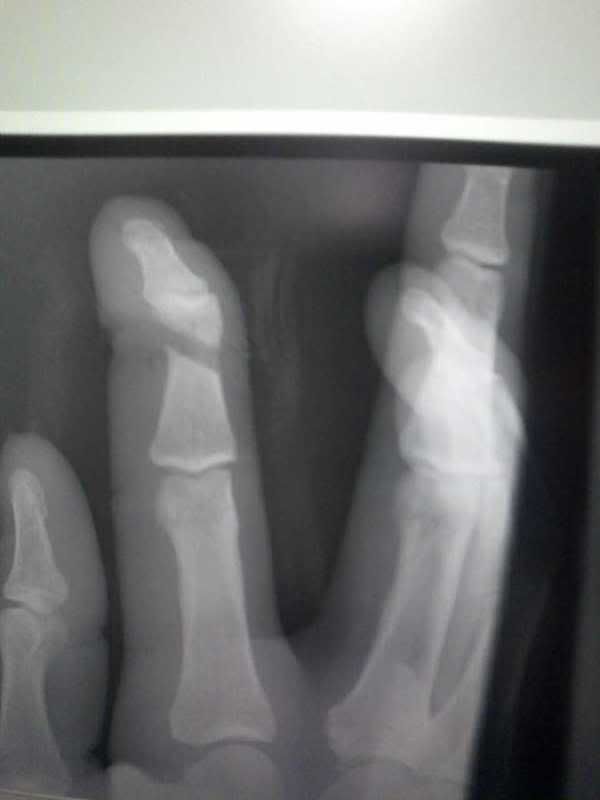

Well I joined the injury club last night. Was wrapping up a piece of cocktail glass for shipment when I dropped the roll of shrinkwrap. Well in my infinite wisdom I did not want it to slam into my kitchen floor, so I went to grab the falling roll. As I went to grab it the roll slammed into my foot and a millisecond later my hand smashed into the top of the roll. After wailing in pain and almost passing out I finally took my sock off to see what I had done. Ripped the top skin right off the big toe and blood, but not bleeding too bad. So I was starting to think it was just a skin abrasion. After about a half hour I told the wife to drive me to the immediate care center. Was a good choice because after 2hrs there I limped out with a broken toe and a broken finger, both on my left side.

I tried to get the xray pics posted but the software they game me with them only allows me to view it. I am off work today so I will play around with it some more.